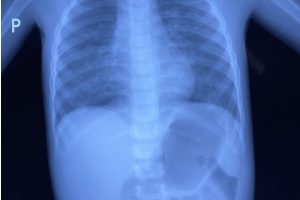

Lúc 16 giờ 08/05/2021, bệnh viện Nhi đồng Thành phố tiếp nhận một trường hợp trẻ Tr. K. Ng 3 tuổi, nữ, ngụ ở Long An, nhập viện trong tình trạng đau bụng, nôn...